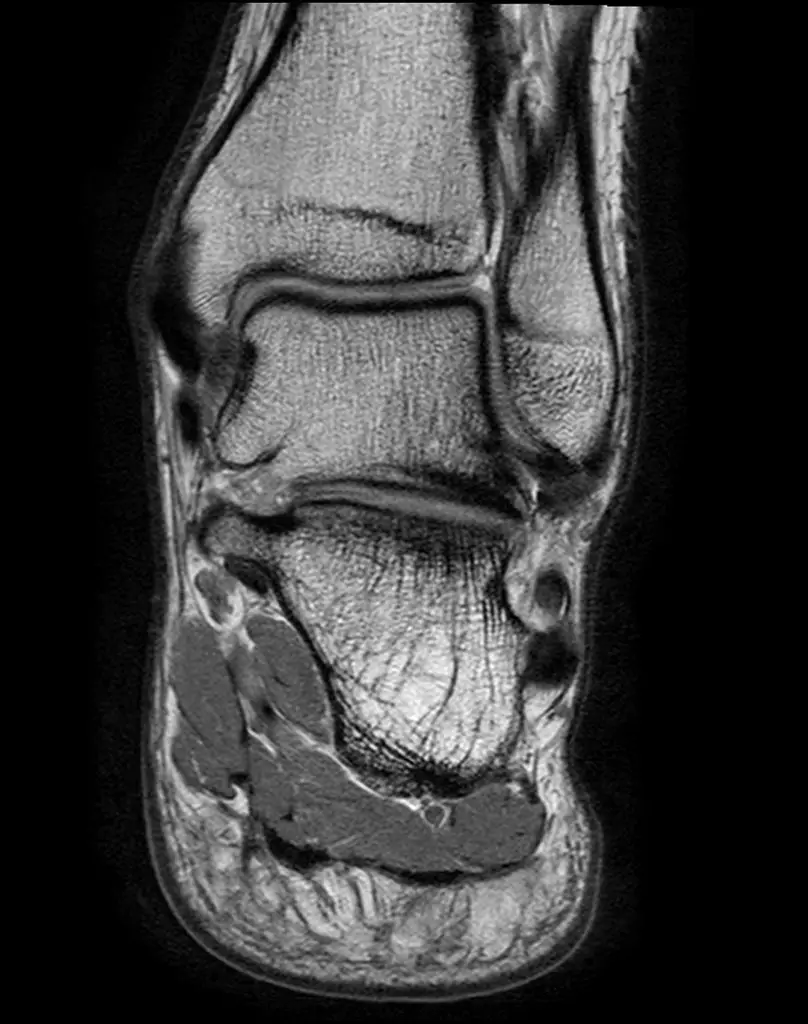

МРТ стопы

Помимо голеностопного сустава, визуализируются структуры предплюсны, плюсны и фаланг, включая сочленения, сухожилия, мягкие ткани (айхиллово сухожилие, плантарная фасция и т.д.).